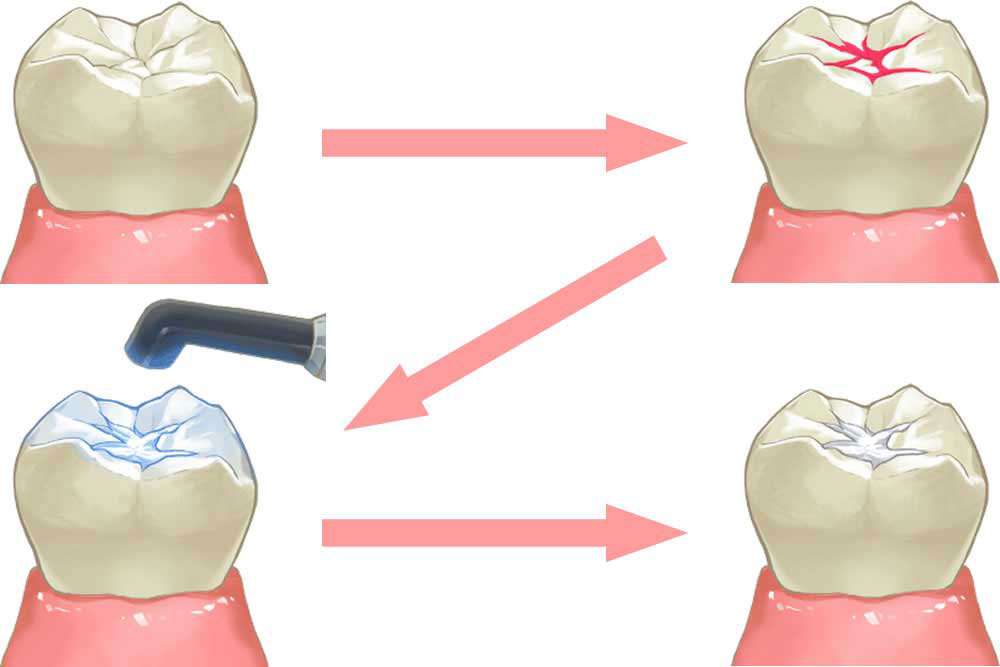

シーラント充填で虫歯予防

乳歯の奥歯や、生え変わったばかりの永久歯は、歯の表面に小さな溝が存在し、食べかすなどの汚れが溜まりやすくなります。汚れが溜まる事で虫歯リスクが高くなるため、シーラントと言う歯科用の樹脂で、あらかじめ歯の溝を埋める処置を実施して、予防効果を高めます。